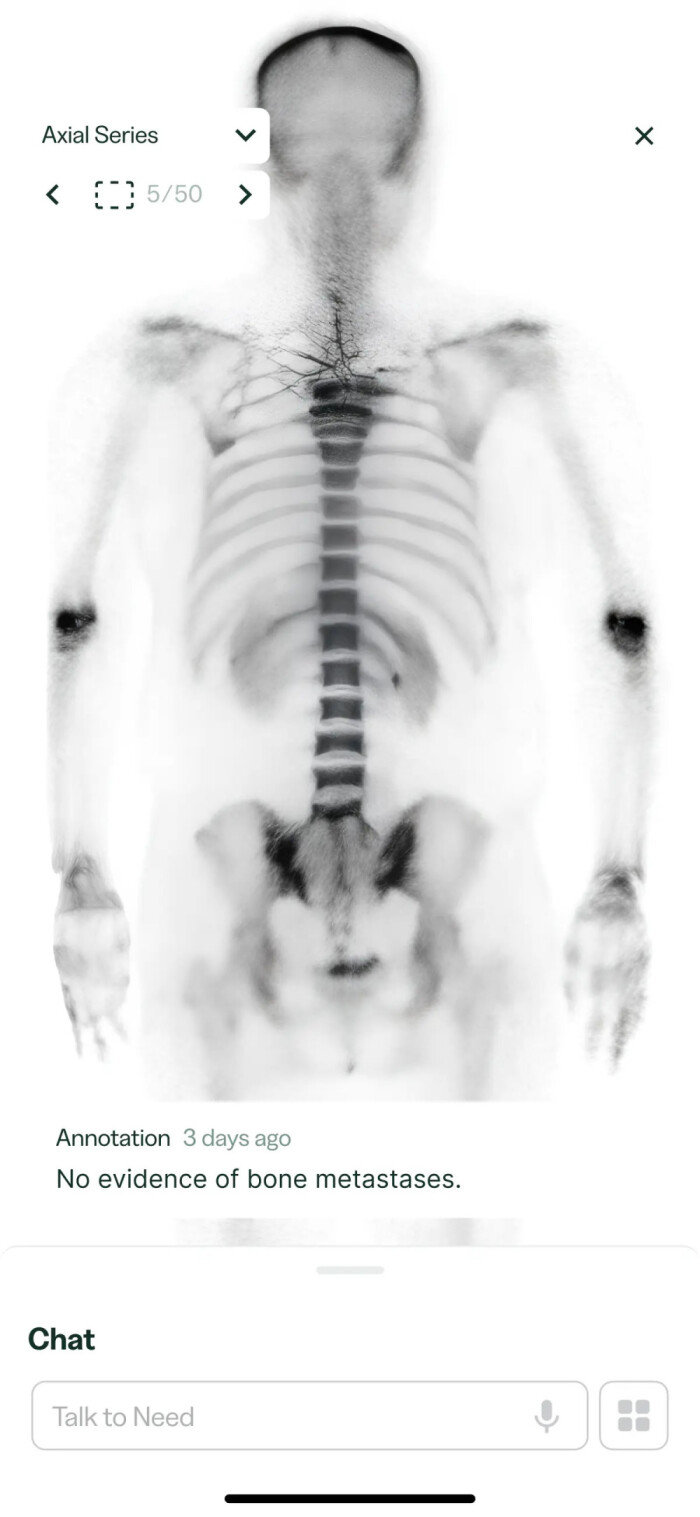

인공지능(AI) 기반 의료 정보 제공 기업 니드(Need)의 ‘암보호시스템’ 애플리케이션(앱) 화면. 니드 제공

니드의 암보호시스템 앱 화면. 영어로 “뼈 전이 증거가 없습니다”라고 적혀 있다. 니드 제공